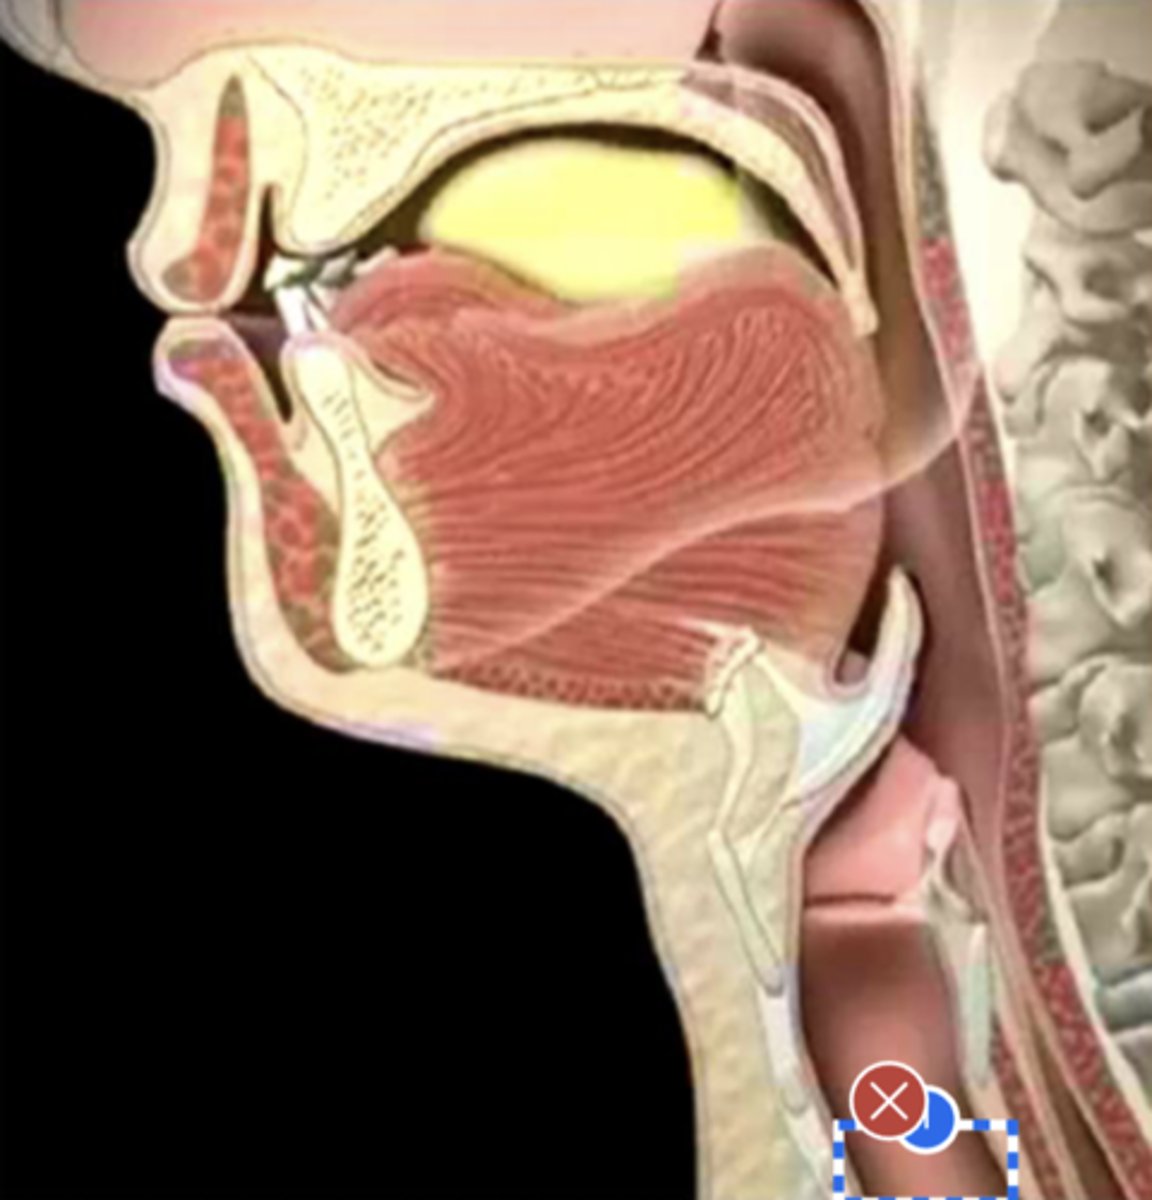

Label base of tongue (lateral view)

label anterior tongue (lateral view)

Label posterior/ back of tongue (lateral view)

Label Mandible (lateral view)

Label velum/ soft palate (lateral view)

Label hyoid bone (lateral view)

Label epiglottis (lateral view)

Label thyroid cartilage (lateral view)

Label posterior cricoid (lateral view)

Label trachea (lateral view)

Label upper esophageal sphincter (lateral view)

Label esophagus (lateral view)

Label posterior pharyngeal wall (lateral view)